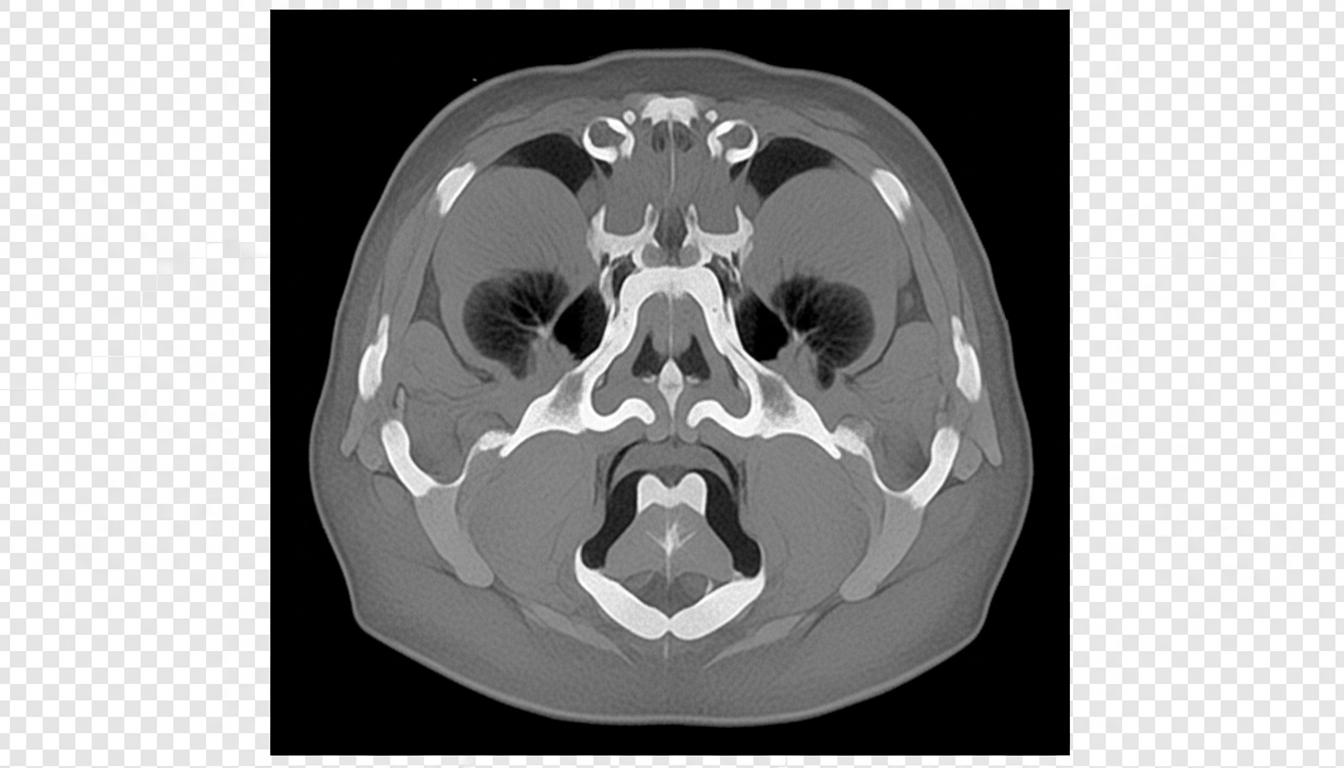

Tomografia zatok, znana również jako tomografia komputerowa (CT), to zaawansowane badanie obrazowe wykorzystujące promieniowanie rentgenowskie do uzyskania precyzyjnych, przekrojowych obrazów zatok przynosowych – zarówno kości, jak i tkanek miękkich. W odróżnieniu od tradycyjnego RTG, skaner tomografu obraca się wokół głowy pacjenta, wykonując setki zdjęć, które komputer łączy w trójwymiarową wizualizację obszaru zatok.

Najdokładniejsze badanie obrazowe zatok, pokazujące detale kości i tkanek miękkich. Wykorzystuje wysoką dawkę promieniowania rentgenowskiego. Skaner CT

Zaawansowane urządzenie obracające się wokół głowy pacjenta, wykonujące setki zdjęć pod różnymi kątami. Obraz 3D

Komputer łączy poszczególne zdjęcia, tworząc trójwymiarowy model pozwalający na precyzyjną ocenę zmian chorobowych.

Dzięki tej technologii lekarz może zobaczyć nawet mikroskopijne zmiany w strukturze zatok, polipy, guzy lub powikłania zapalenia. Jednak nie zapominajmy – precyzja ma swoją cenę, a każda ekspozycja na promieniowanie to kalkulowane ryzyko.